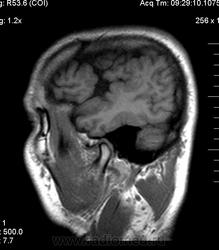

Мужчина 32 лет. Из анамнеза: перинатальное повреждение ЦНС, ДЦП, дизартрия, правосторонний верхний монопарез. С 16 лет приступы эпилепсии.

Аплазия прозрачной перегородки. Шизэнцефалия с открытыми краями в лобно-теменной области слева. Шизэнцефалия с закрытыми краями в лобной области справа? Утолщение коры по контуру расщелин и в области глазничной извилины правой лобной доли. Микрогирия? Гиперостоз костей свода черепа. Уважаемые коллеги, возможно я ошибаюсь, или есть еще аномалия?

На мой взгляд, полимикрогирия двусторонняя (конвекситальные отделы дорзальных отделов лобных долей и частично теменных, а также в базальном отделе полюса правой лобной доли) + закрытая шизенцефалия левой лобно-теменной области. Аплазия прозрачной перегородки (как признаки лобарной голопрозенцефалии).